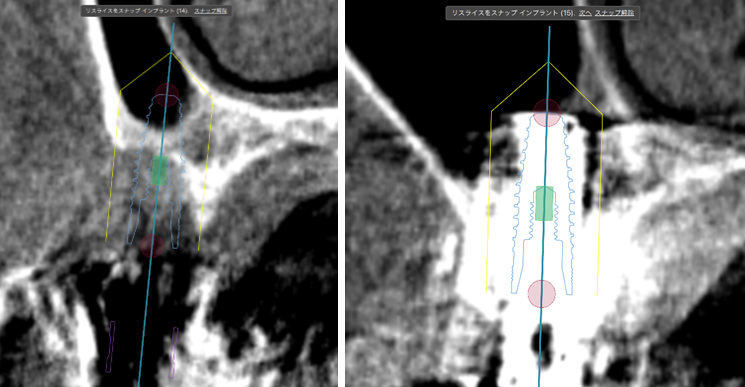

①歯槽頂よりサイナス

リフトを行いました。

②血液成分とカルシウム材料により骨造成をしました。

③ガイデッドサージェリーにてインプラント埋入しました。